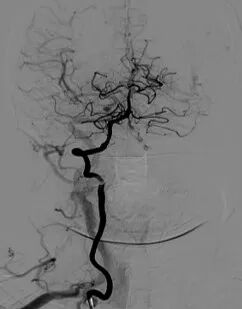

◆ 左侧颈内动脉C4段狭窄解除。

导丝怎么扩重磅!NOVA颅内药物球扩支架湖北首例植入!_https://www.jmylbn.com_新闻资讯_第12张

支架释放回收球囊后造影

◆ 远端分支显影良好。

导丝怎么扩重磅!NOVA颅内药物球扩支架湖北首例植入!_https://www.jmylbn.com_新闻资讯_第13张

左侧颈内动脉系统造影